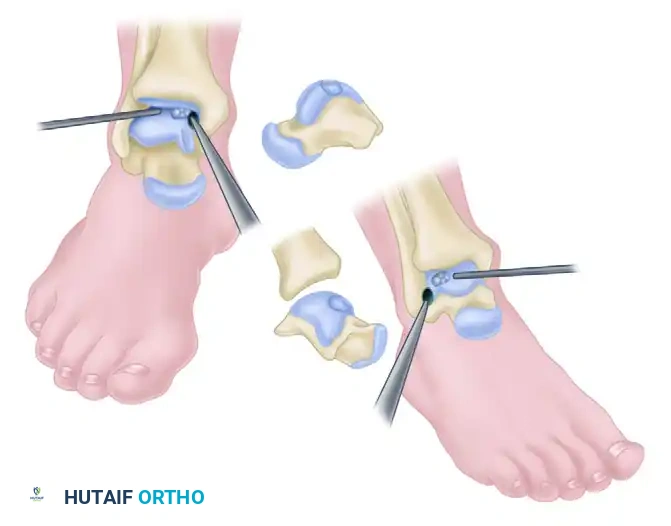

Step 1: Recipient Site Preparation

Once the lesion is fully exposed, utilize a commercially available recipient sizer to determine the exact diameter of the defect. Harvesters are typically available in sizes ranging from 5 to 11 mm (larger sizes are available for massive defects, though multiple overlapping plugs—the "snowman" technique—may be used).

Place the recipient harvester strictly perpendicular to the articular surface for dome lesions, or at a 45-degree angle for talar shoulder lesions.

Impact the tubular chisel to extract the recipient core to a precise depth of 10 mm. Remove the core, leaving a perfectly cylindrical defect. Drill multiple small holes into the subchondral bone at the base of the recipient hole to stimulate marrow bleeding and enhance graft integration.

Step 2: Donor Graft Harvesting

Attention is turned to the ipsilateral knee. The graft is harvested either arthroscopically or through a small mini-arthrotomy.

* Donor Sites: The periphery of the medial femoral condyle, the lateral femoral condyle (proximal to the sulcus terminalis), or the lateral trochlea (specifically for talar shoulder lesions to match the contour).

Use the specially designed donor harvester corresponding to the exact diameter of the recipient hole (5 to 11 mm). Drive the harvester perpendicularly into the donor site to a depth of 10 to 12 mm.

Surgical Pearl: The donor graft should be harvested 1 to 2 mm deeper than the recipient hole (e.g., 12 mm donor depth for a 10 mm recipient hole). This ensures that the subchondral bone of the graft bottoms out in the recipient socket, providing structural stability while allowing the cartilage cap to sit flush.

Extract the donor plug. Inspect the cylindrical graft within the harvester to ensure the cartilage cap is intact and the bone cylinder is structurally sound.

Step 3: Graft Insertion and Seating

Bring the donor harvester containing the graft to the ankle. Align the harvester perfectly with the recipient socket.

Insert the cylindrical graft carefully into the recipient hole using the specially designed extruder or collared pin through the back of the donor harvester.

CRITICAL PITFALL: Do not remove the OATS harvester from the recipient site before the completion of full graft extrusion. Furthermore, do not allow the harvester to deviate from the insertion angle during extrusion. Either of these technical errors will place sheer stress on the graft and cause a catastrophic fracture of the donor core.

Once the graft is extruded into the socket, use the oversized sizer-tamp to gently tap the core until it is perfectly flush with the surrounding native cartilage. A proud graft will cause "kissing lesions" on the tibial plafond, while a sunken graft will fail to bear load, leading to fibrocartilage infill and cyst formation.